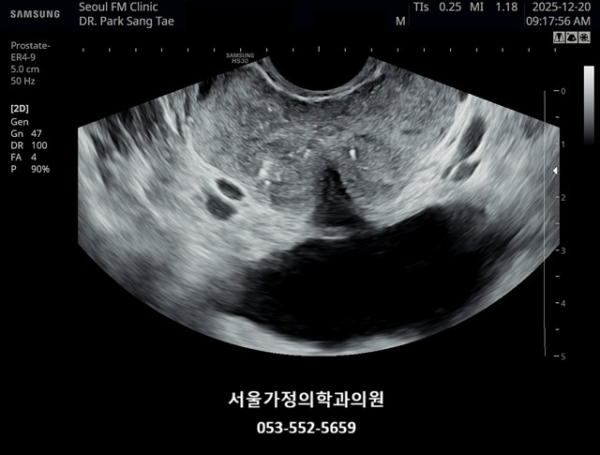

내원 첫 당일 경직장 전립선 초음파 검사상 사정관 입구의 결석들과 사정관 낭종이 관찰되는 사진입니다.(NIH:24)

On the initial transrectal prostate ultrasound, the image shows the presence of calcifications (stones) at the opening of the ejaculatory duct as well as a cystic lesion within the ejaculatory duct (ejaculatory duct cyst).(NIH:24)

주 2회 14주 동안 전립선과 정낭, 사정관과 정관등의 표적 치료후 사정관의 낭종등이 치료 되고 있는 경직장 전립선 초음파 검사 자료 입니다.(NIH:13)

This transrectal prostate ultrasound image shows improvement of an ejaculatory duct cyst after targeted treatment of the prostate, seminal vesicles, ejaculatory ducts, and vas deferens.

The treatment was performed twice a week over a period of 14 weeks. As a result, the previously noted cyst in the ejaculatory duct is gradually resolving, indicating improved drainage and recovery of normal ductal circulation.(NIH:13)

For the patient, this means that small stones and a cyst are blocking the natural passage where semen normally flows. These findings can explain symptoms such as pelvic pain, difficulty with ejaculation, blood in semen, or infertility.

Treatment may involve addressing these blockages to restore normal flow and relieve associated symptoms.